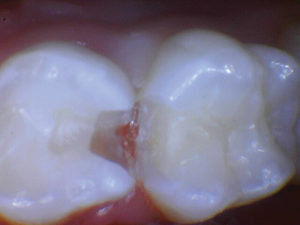

Caso 1

Un paciente de 8 años presentó descomposición de OD en un primer molar primario con síntomas de pulpitis reversible. El diente fue el tratamiento planificado para una restauración de OD con Activa Bioactive Restorative (Pulpdent). Tras la excavación por descomposición, se produjo una exposición pulpar que requirió una pulpotomía terapéutica. Debido a la edad del paciente, me sentí cómodo con una pulpotomía terapéutica con Biodentine (Septodont) seguida de una restauración estética. Si el paciente hubiera tenido entre cuatro y cinco años, me habría restaurado con una corona de acero inoxidable debido a su historial comprobado de longevidad.

Figura 1 Vista preoperatoria del primer molar primario superior. |